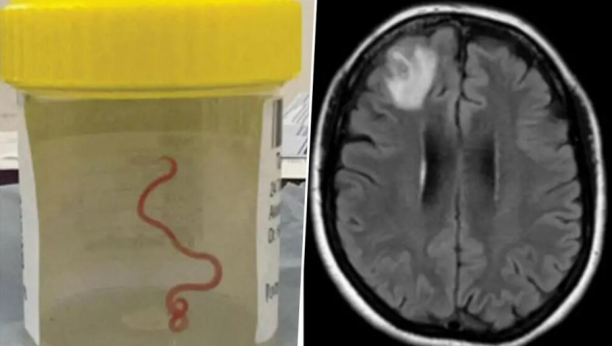

Neurohirurg iz Australije izvukao je osam centimetara dugog parazitskog okruglog crva iz glave 64-godišnjeg pacijenta, nakon što je nesrećna žena mesecima trpela neobične simptome, bez ikakvog napretka zdravstvenog stanja.

- O moj Bože, nećeš verovati šta sam upravo našao u mozgu jedne gospođe — živo je i izvija se - izjavio je neurohirurg, Hari Prija Bandi, koji je i obavio zahvat.

Do 2022. godine njeni simptomi su takođe uključivali zaboravnost i depresiju, što je dovelo do upućivanja u bolnicu u Kanberi. MRI skeniranje njenog mozga otkrilo je abnormalnosti koje zahtevaju operaciju.

- Ali neurohirurg sigurno nije ušao tamo misleći da će pronaći crva koji se migolji. Neurohirurzi se redovno bave infekcijama u mozgu, ali ovo je bio nalaz koji se dešava jednom u karijeri. Niko nije očekivao da će to pronaći - rekao je Senanjake.

- Potražili udžbenike, tražeći sve različite vrste okruglih crva koje mogu izazvati neurološke invazije i bolesti. Kanbera je malo mesto, pa smo crva, koji je još bio živ, poslali pravo u laboratoriju naučnika CSIRO-a koji je veoma iskusan sa parazitima. Samo ga je pogledao i rekao: 'O moj Bože, ovo je Ophidascaris Robertsi - rekao je Senanajake.

Ophidascaris robertsi je okrugli crv koji se obično nalazi kod pitona.